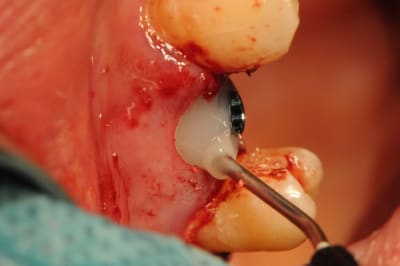

juste pour illustrer mon propos....

ici une MCI ou plutôt, devrais je dire une vis de cica anatomique immédiate.